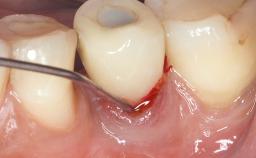

Late Presentation of Peri-Implant Mucositis Requiring Soft-Tissue Augmentation and Esthetic Crown Lengthening at Implant Site 11

Biological or technical complications around implant-supported prostheses place a significant burden on patients as well as the surgical and restorative team. Inflammation of the peri-implant soft tissues is often the first sign that something has gone awry. While there is never a good time for a complication, late presentation of inflammation in the soft tissues around a long-standing prosthesis triggers a period of research and review of the case in order to ascertain the treatment history and its possible contribution to the etiology of the situation. This becomes more complicated in situations where a patient has not received regular maintenance and clinical/radiographical examinations due to personal, financial, or professional reasons. When the complication occurs in the esthetic zone, the complexity of the situation expands exponentially, as the only acceptable outcome in the patient’s eyes will be the maintenance of the esthetics of the prosthesis.